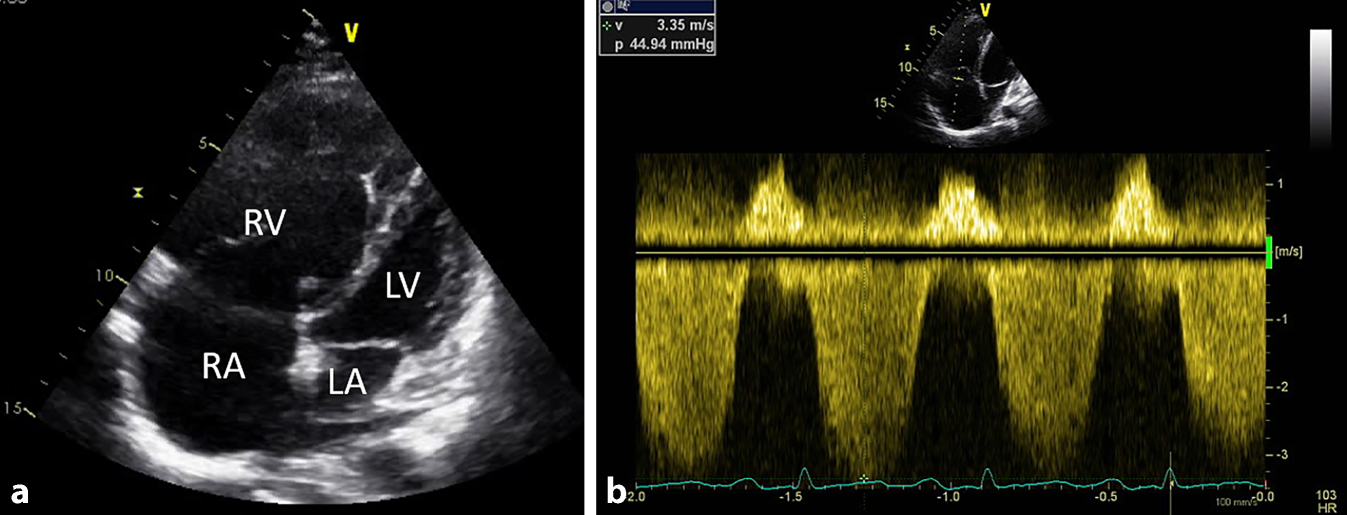

Der Goldstandard für die Diagnose einer PH, egal welcher Ursache, ist die invasive Rechtsherzkatheteruntersuchung. Wichtige Hinweise auf eine PH liefern im klinischen Alltag Routineuntersuchungen wie die Auskultation (betonter zweiter Herzton, Pansystolikum aufgrund der Trikuspidalklappeninsuffizienz), das EKG (Rechtstyp, rechtsventrikulärer „strain“ V2–V4, [in]kompletter Rechtsschenkelblock), die Röntgenuntersuchung des Thorax (Dilatation des Truncus pulmonalis, Rechtsherzhypertrophie) und die Laboruntersuchung (erhöhtes NT-pro-BNP). Die Lungenfunktion zeigt bei PH, wenn nicht gleichzeitig eine Lungenerkrankung vorliegt, einen unauffälligen Befund (evtl. leichtgradige Restriktion). Die DLCO ist jedoch meist leicht- bis mittelgradig reduziert, was oft mit einer respiratorischen Partialinsuffizienz einhergeht (pO2 vermindert, pCO2 normal oder ggf. durch Hyperventilation vermindert). Das wichtigste nichtinvasive diagnostische Tool stellt die Rechtsherzechokardiographie mit Abschätzung des systolischen Pulmonalarteriendrucks (sPAP) und der rechtsventrikulären Funktion und Dimensionen des rechten Herzens dar (Abb. 2). Ist das Trikuspidalinsuffizienzsignal > 3,4 m/s, ist die Wahrscheinlichkeit des Vorliegens einer PH hoch. Aufgrund des erhöhten Risikos, eine PH zu entwickeln, sollten SSc-PatientInnen einmal jährlich auf das Vorliegen einer PH mittels Echokardiographie gescreent werden [2].

Abb. 2

4‑Kammer-Blick in der transthorakalen Echokardiographie einer SSc-PatientIn mit schwerer pulmonal-arterieller Hypertonie. a Stark vergrößerter rechter Vorhof und Ventrikel mit D‑Sign als Zeichen der Druckerhöhung. Linker Ventrikel und Vorhof sind komprimiert. b Trikuspidalinsuffizienz-Jet in der CW-Doppler-Sonographie bei ~ 3,35 m/s (umgerechneter systolischer Druck von ~ 45 mm Hg) als Hinweis auf einen erhöhten pulmonalen Druck. RV rechter Ventrikel, RA rechtes Atrium, LV linker Ventrikel, LA linkes Atrium. (© Klinische Abteilung für Pulmonologie, Medizinische Universität Graz)

Bild vergrößern

Erhärtet sich der Verdacht auf eine PH, sollte die Vorstellung im spezialisierten Zentrum zur weiteren invasiven Abklärung mittels Rechtsherzkatheter erfolgen. Da SSc-PatientInnen eine besonders vulnerable Gruppe darstellen und einer möglichst frühzeitige PH-Abklärung bedürfen, kann die Überweisung sehr niederschwellig gehalten werden [9].